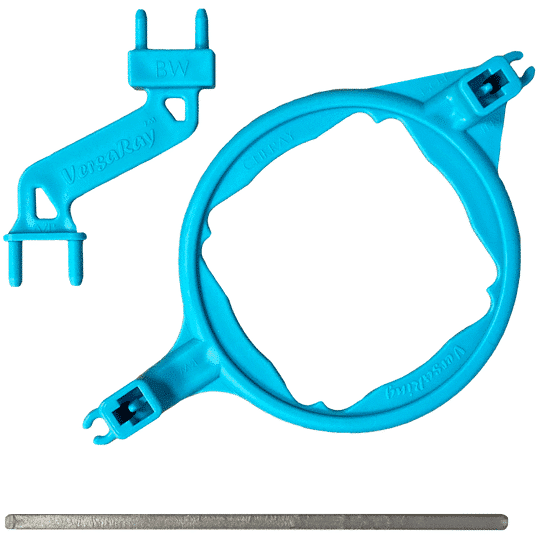

The Pro sensor combines ultra-low noise technology for crisp images with lower radiation, true-clipped corners for easier positioning, a 45° cord exit for vertical shots, and direct software integration, all designed for comfort, durability, and reliability. Plus, it's proudly made in the USA.

All of our sensors are a great fit for any office. The DentiMax Pro Sensor is our premier sensor and offers a full range of sizes and comfort. This sensor allows you to take images on small children all the way up to adults. It is designed with patient comfort in mind and also created to give offices the ease, quality, and reliability they deserve.